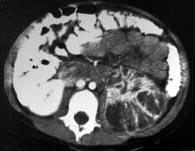

问题 男,5岁,有尿路感染伴急性发热,CT增强扫描如图所示,最可能诊断为 ( )

选项 A、左侧黄色肉芽肿性肾盂肾炎 B、左侧慢性肾盂肾炎 C、左侧肾脓肿 D、左侧急性肾盂肾炎 E、左侧肾炎

答案 D